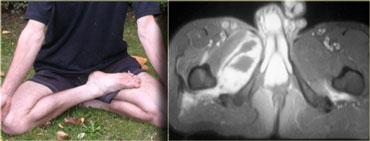

Laceration

Bên trái là hình ảnh của một bệnh nhân bị thương do dao.

Người đàn ông này bị vợ bắt gặp khi đang ngoại tình với người phụ nữ khác và bị đâm vào vùng bẹn.

Hậu quả là cơ lược bên phải của ông bị rách.

Chụp cộng hưởng từ thường không được chỉ định trong trường hợp vết rách, vì những bệnh nhân này thường được đưa thẳng đến phòng cấp cứu hoặc phòng mổ để phẫu thuật thăm dò, nhưng trường hợp này minh họa rõ nét hình ảnh cơ bị teo và mô sẹo.